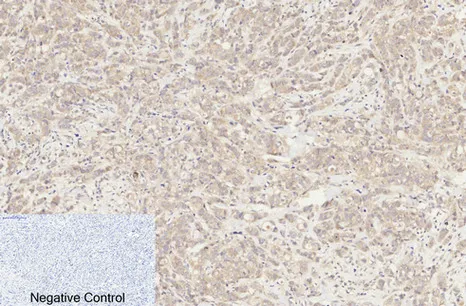

Endoglin Rabbit Polyclonal Antibody

Cat: APRab10463